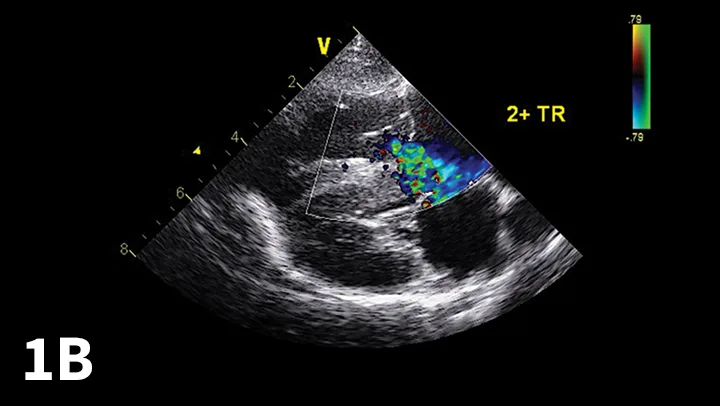

From the clinicians standpoint, echocardiography should be considered the most useful method to document PHTN (Figure 1).

Echocardiographic Doppler study documenting high tricuspid regurgitant velocity consistent with pulmonary hypertension. The modified Bernoulli equation [change in pressure = 4 (regurgitant velocity)2] may be used to estimate the systolic PAP. In the example shown, the tricuspid regurgitant velocity is 4.1 m/sec; thus, estimated PAP is 67 mm Hg.